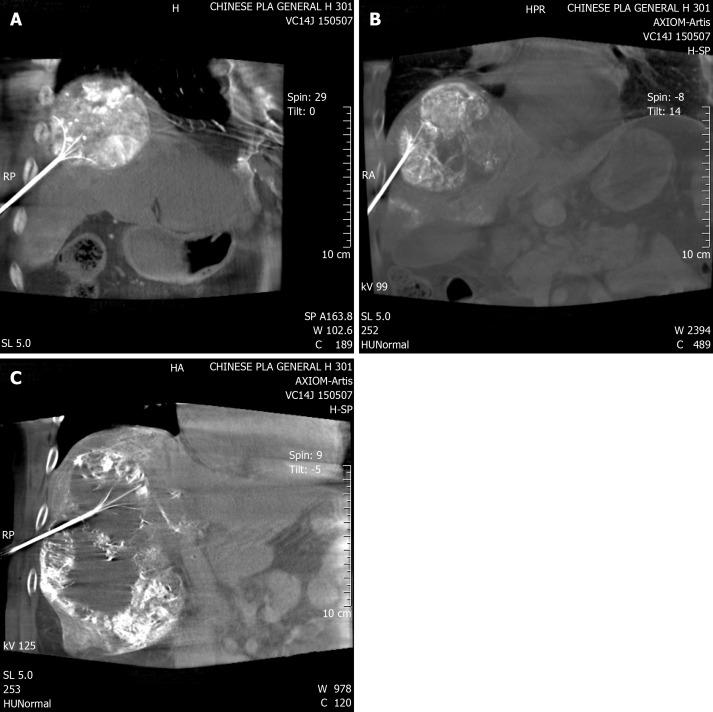

To evaluate recurrence and mid-term survival of patients with large HCC treated by transcatheter arterial chemoembolization (TACE) and radiofrequency ablation (RFA).

This was a retrospective study. From 2010 to 2013, 46 consecutive patients with large HCC were treated with simultaneous TACE and RFA. Thirty-five of 46 patients had a single tumor. Progression-free survival (PFS) and overall survival (OS) were analyzed at 2 years and 3 years, respectively.

Forty-six patients treated by simultaneous TACE and RFA had no significant complications and treatment was successful. After 3 years, median PFS and OS were 10.21 ± 1.58 mo and 26.44 ± 2.26 mo, retrospectively. The survival rate was 67.5% after 2 years and 55.67% after 3 years.

These preliminary data show that simultaneous TACE and RFA are safe and effective for large HCC.